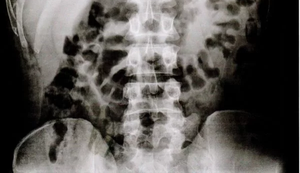

101 presos de SP voltam com objetos escondidos no estômago